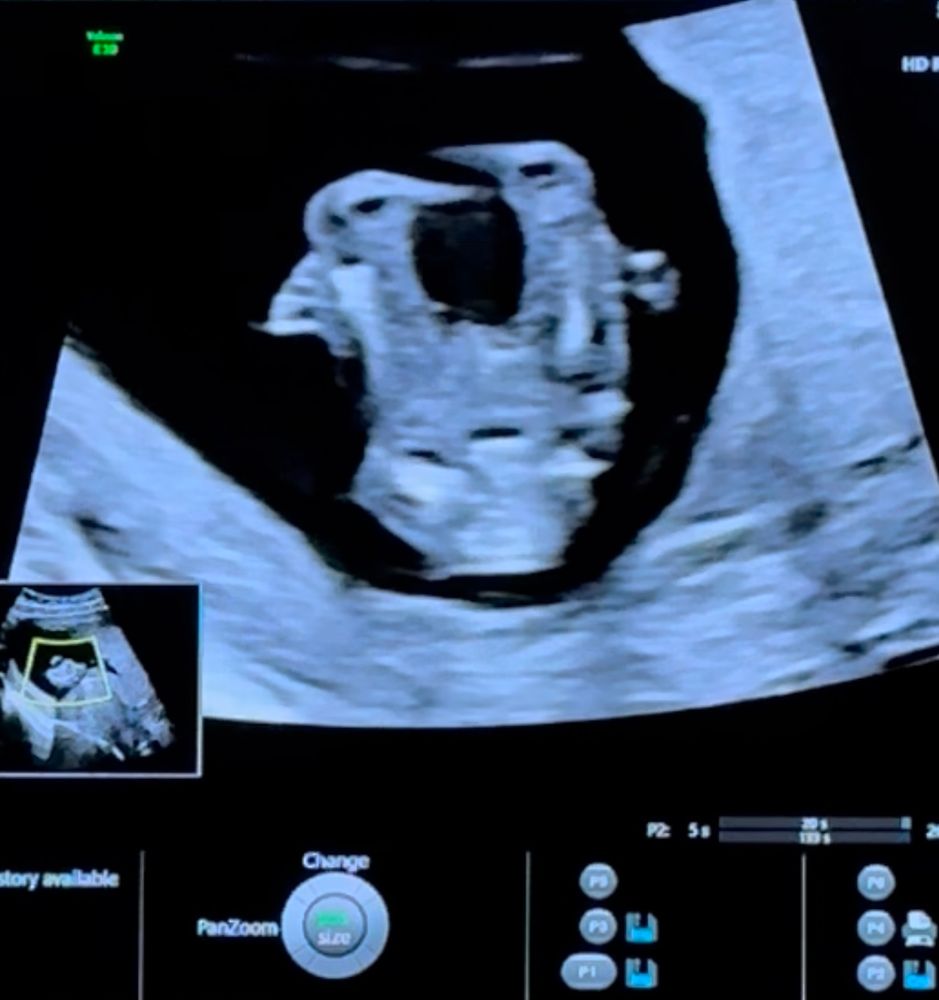

Пол ребенка в 12 недель (половой бугорок), мальчик или девочка?

за ножкой не видно бугорка(

Так не видно же.

Вроде как на девочку похоже, у мальчиков бугорок "крючёчком" вверх

Сбоку ножкой закрылся, а снизу на таком сроке не смотрят ☺️